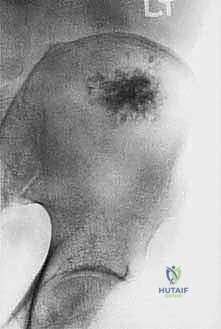

- Plain Radiography (FIG 2): While of limited value for early lesions, it provides an initial overview. As you can see in Figure 2A, we have a large lytic lesion of the right periacetabular region. Figure 2C shows a cartilage-forming lesion in the left ilium. However, plain films often underestimate the true extent of these tumors.

* CT with Intravenous Contrast and 3D Reconstruction (FIG 3): This is our workhorse for assessing bone involvement, destruction, and the critical relationship between the tumor and major pelvic blood vessels. It reveals any distortion of the pelvic anatomy and guides resectability. Figure 3A clearly shows extensive bone destruction and tumor extension into the pelvis and gluteal region. Figure 3C highlights an extensive tumor on the medial aspect of the ilium with destruction of the inner table.